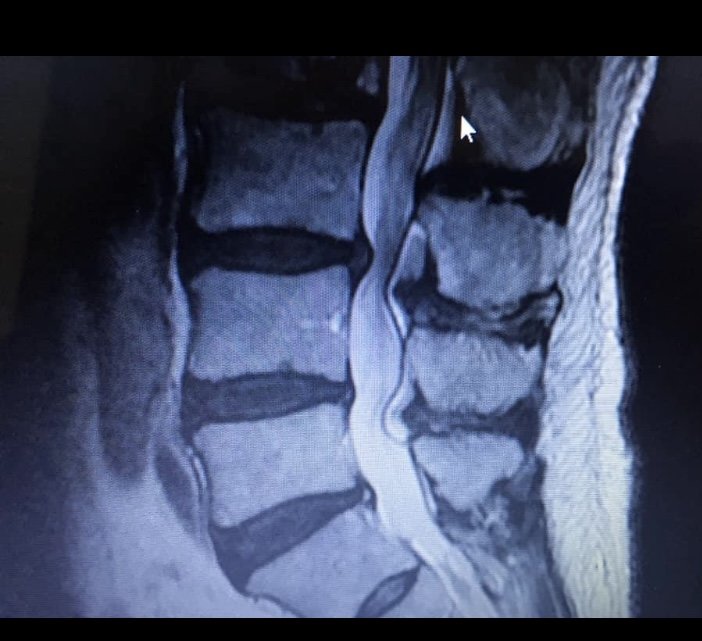

Pulp, SASS#28319 Posted February 1 Posted February 1 This was my back. Doc went in and cleaned up all the restrictions in about 30 minutes. Back was really sore for awhile, I took hydrocodone for three nights to help sleep, did OK after that. started therapy two weeks after surgery for about 4 weeks. I still have some occasional mild lower back pain, but zero sciatica. 2 2 Quote